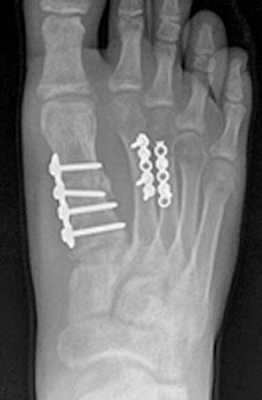

Открытая репозиция перелома

Открытая репозиция при переломе плюсневой кости стопы, накостный остеосинтез пластиной и винтами. Операция включает в себя хирургический разрез, доступ к сломанной плюсневой кости аккуратно отводя сухожилия, сосуды и нервы, мобилизацию костных отломков, устранение смещения и фиксация в правильном положении.

Гипсовая иммобилизация не проводится, так как металлоконструкция, фиксирует отломки.

Разрешается ходьба с опорой на пяточную область в течение месяца.

Это возможно благодаря множеству поперечных связок, выполняющих роль стабилизаторов отломков, благодаря шинированию с неповреждёнными плюсневыми костями. При повреждении более чем одной плюсневой кости, значимом смещении (более 4 мм), методом выбора становится оперативное лечение. Для оперативного лечения могут использоваться как вводимые интрамедуллярно спицы, винты или стержни (в случае ротационно относительно стабильных переломов), так и минипластины (как компрессирующие так и блокируемые) или же использование компрессирующих винтов (2-3) без пластины. В послеоперационном периоде требуется ходьба в ортезе без нагрузки до появления признаков консолидации.

Для остеосинтеза чаще всего используются компрессирующие винты и пластины.